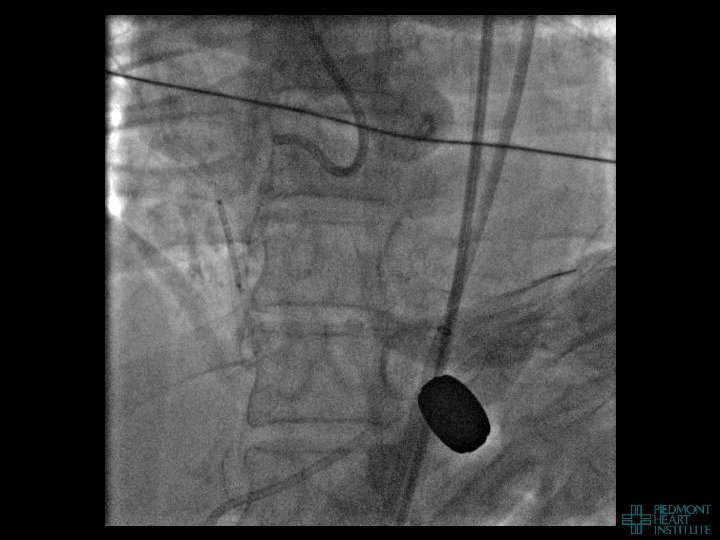

Case Example 3